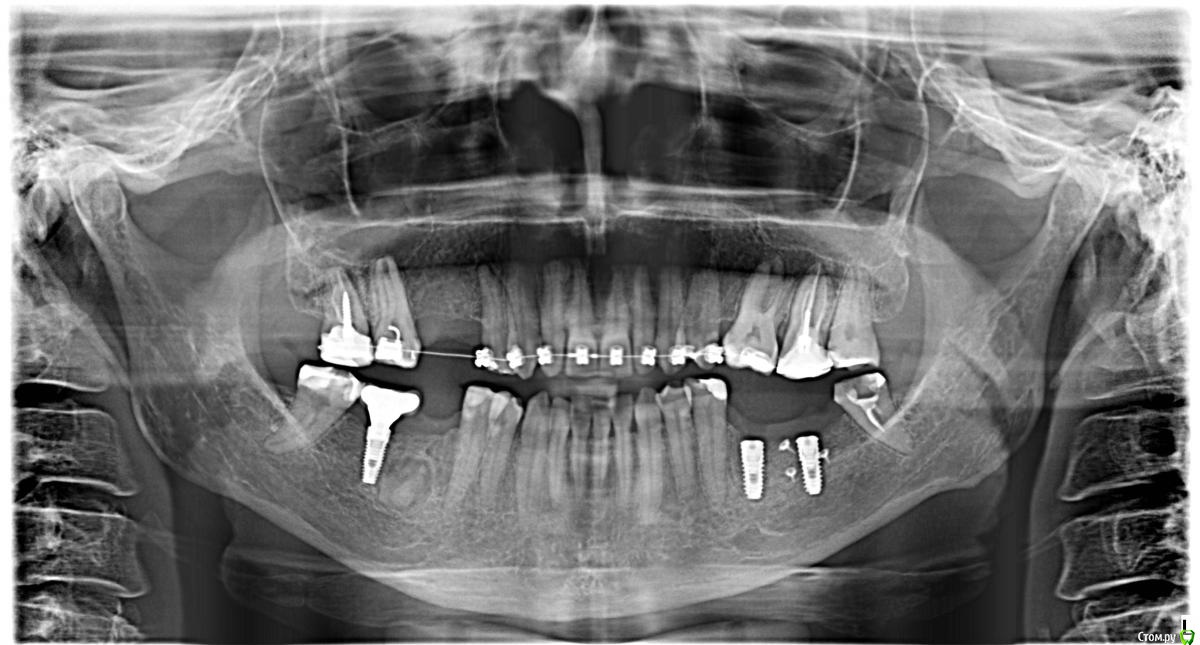

bullbull Опубликовано 5 октября, 2017 Поделиться Опубликовано 5 октября, 2017 Здравствуйте. Пациентка 50 лет (примерно) проходит ортодонтическое лечение. Планируется имплантация в области 46. На панораме и КТ образование как раз на уровне 46. За год в размере не изменилось. Никак не беспокоит.Что это может быть? Фолликулярная киста? Корень? Ссылка на комментарий

dok1 Опубликовано 5 октября, 2017 Поделиться Опубликовано 5 октября, 2017 Очень может быть корень. Сам недавно столкнулся с ситуациями один в один. В одной ситуации имплант всё же поставил. В другой - нет. Вычистился и зашился. Позже закручусь. 1 Ссылка на комментарий

kramer Опубликовано 5 октября, 2017 Поделиться Опубликовано 5 октября, 2017 Похоже на корень Ссылка на комментарий

Дмитрий Л. Опубликовано 19 октября, 2017 Поделиться Опубликовано 19 октября, 2017 Ds: одонтома-?Я бы направил в стационар... Хотя бы для гистологии. 1 Ссылка на комментарий

bullbull Опубликовано 31 октября, 2017 Автор Поделиться Опубликовано 31 октября, 2017 Сорри!Корень. С окружающими тканями не связан. В процессе удаления распилил, канал есть. Но импл сразу не ставил. 1 Ссылка на комментарий